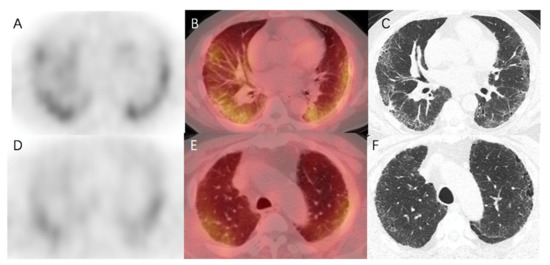

2.4. 99mTc-HFAPI Uptake in IPF Patients

In healthy human subjects, there is no pulmonary 99mTc-HFAPI uptake (Figure S2). So, any region of tracer uptake within the lungs was considered abnormal. IPF patients exhibited raised pulmonary 99mTc-HFAPI uptake, with a subpleural and peripheral distribution, involving especially the base of both lungs, as shown in Figure 4. In the corresponding areas of elevated tracer uptake, fibrotic abnormalities, including reticular opacity, traction bronchiectasis, and honeycombing, were observed in HRCT images.

In addition, the degree of increased uptake was associated with fibrotic severity. In Figure 5, fibrotic regions were found in the subpleural of basal parts, and corresponding elevated 99mTc-HFAPI uptake was observed, with an SUVmax of 4.5 and LBR of 3.0 in the right lung and an SUVmax of 4.4 and LBR of 2.9 in the left lung. A minor abnormality was also found in the apex parts, with less tracer uptake (SUVmax of 3.4 and LBR of 2.3 in the right lung and SUVmax of 3.7 and LBR of 2.5 in the left lung).

Figure 5. 99mTc-HFAPI SPECT/CT and HRCT images of a 65-year-old IPF patient. High 99mTc-HFAPI uptake (SUVmax of 4.5 and LBR of 3.0 in the right lung and SUVmax of 4.4 and LBR of 2.9 in the left lung) in the subpleural of basal parts corresponded to the areas of reticular opacity on HRCT images (AC). Minor abnormality in HRCT images in the apex parts level demonstrated an SUVmax of 3.4 and LBR of 2.3 in the right lung and SUVmax of 3.7 and LBR of 2.5 in the left lung (DF).